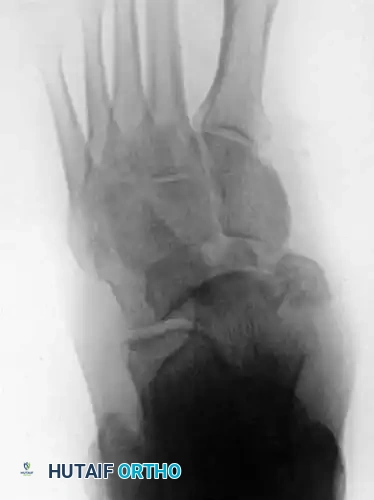

Fig. 86-36 Open reduction and internal fi xation of type III navicular fracture. A and B, Preoperative radiographs. C, Semicoronal CT scan showing comminution of body of navicular. D and E, Postoperative radiographs.

Fig. 86-36: Open reduction and internal fixation of a Type III navicular fracture. Note the severe comminution on the preoperative CT and the restoration of the medial column length postoperatively.